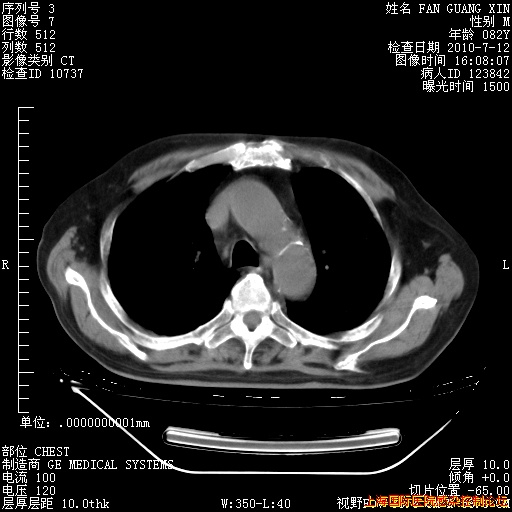

今天复查CT